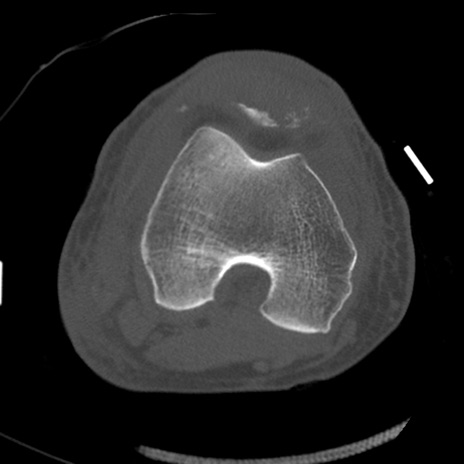

症例28 右膝関節CT(横断像)

右膝関節CT